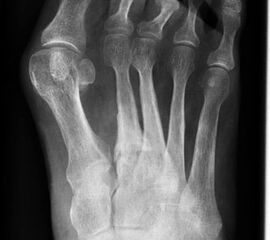

Stoßwellentherapie bei osteochondralen Läsionen

Die Osteochondrosis dissecans tali (OD) ist definiert als lokalisierte Pathologie der Gelenkfläche des Talus, die zur Abtrennung eines kartilaginären Fragmentes und subchondralen Knochens führen kann 93. Es existieren am Körper 3 Prädilektionsstellen für die Entwicklung einer OD mit unterschiedlicher Häufigkeit: Femurkondylen 75%, Talus 12% und Capitulum humeri 12%, sowie sonstigen Lokalisationen 1%. Abhängig vom Zeitpunkt des Auftretens unterscheidet man die juvenile Form (offene Wachstumsfuge) von der adulten Form (geschlossene Wachstumsfuge) (Dotti 2002).

Nach Dotti sind am Talus vorrangig die posteromediale und die anterolaterale Talusschulter betroffen. Die Ätiologie der OD an der anterolateralen Talusschulter scheint vermehrt traumatisch/repetitiv mikrotraumatisch zu sein, die der posteromedialen Talusschulter vermehrt idiopathisch.

Die Stadieneinteilung nach Berndt und Harty umfasst 4 Stadien und ist unabhängig von der Lokalisation der OD anwendbar 94.

Die Stadieneinteilung nach ARCO (Association Internationale de Recherche sur la Circulation Osseuse) berücksichtigt die Kombination aus MRI-Zeichen, Nativradiologie und Knochenszintigraphie 95.

Die Therapie orientiert sich an der Stadieneinteilung und Lokalisation der OD, sowie am Lebensalter des Patienten. Eine aktuelle Metaanalyse zur OD am Talus 96 zeigt ein Durchschnittsalter von 28 Jahren, bei jüngeren Patienten ist ein günstigerer Verlauf zu erwarten. Die höchste Rate an Spontanheilungen wird bei Kindern beobachtet.

Als Alternative zu operativen Maßnahmen wird bei frühen Stadien der OD auch der Einsatz fokussierter Stoßwellentherapie diskutiert, wenngleich es bislang wenig klinische Studien zur ESWT bei OD am Talus gibt.

Die ESWT wird in der Regel in einer Sitzung unter Leitungs– oder Allgemeinanästhesie durchgeführt, wobei nach Empfehlungen der DIGEST eine mittlere Energieflussdichte von 0,35mJ/mm² und eine Anzahl von 2500 Impulsen empfohlen wird. Bei hochenergetischer Behandlung (>0,5mJ/mm²) kann eine Schädigung des Knorpels nicht sicher ausgeschlossen werden 97.

Aufgrund der Datenlage kann die Anwendung der ESWT bei osteochondralen Läsionen des Talus in frühen Stadien (1 und 2 nach ARCO) erwogen werden. Für eine Therapieempfehlung sind allerdings weitere Studien, insbesondere zur Therapie der OD des Talus zwingend erforderlich. Aufgrund der technischen Schwierigkeit der Behandlung bei teilweise schlechter Erreichbarkeit der Läsion, sollte diese Indikation erfahrenen Anwendern vorbehalten bleiben.